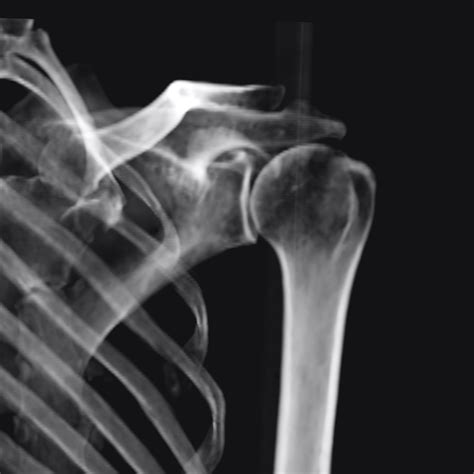

• Dislocations: If the humerus has popped out of the socket, an X-ray confirms the position of the bones and ensures no small fractures occurred during the incident.

It is important to remember that a Shoulder X Ray only visualizes hard tissue (bones). It does not provide detailed information about soft tissues such as the rotator cuff tendons, labrum, or bursa. If the X-ray results appear normal but you are still in severe pain, your doctor may recommend an MRI or Ultrasound to investigate soft tissue injuries that do not show up on conventional X-rays.